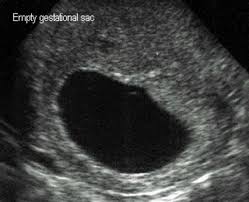

Can a blighted ovum cause an early miscarriage? Nov 10, 2020 · how long can you carry a blighted ovum? Many women need support and time to grieve. It's also called anembryonic pregnancy or empty sac. What to do with a blighted ovum pregnancy? The placenta and sac still give off pregnancy hormones. Dec 13, 2017 · the sonogram will show the placenta and empty embryonic sac. While you can technically get pregnant again as soon as your periods return, we recommend that you wait for about three months to fully heal after a miscarriage.

Dec 13, 2017 · the sonogram will show the placenta and empty embryonic sac. While a blighted ovum leads to loss of pregnancy, most women tend to have healthy pregnancies and babies subsequently. What are the treatment options? Nov 10, 2020 · how long can you carry a blighted ovum? While you can technically get pregnant again as soon as your periods return, we recommend that you wait for about three months to fully heal after a miscarriage. A miscarriage is when a pregnancy ends on its own within the first 20 weeks. How long can a blighted ovum pregnancy last? These cause a pregnancy test to show positive, and can give you symptoms of pregnancy. You have a placenta and a gestational sac, but the embryo doesn't grow. Your body understands the pregnancy is not developing properly and starts to shed blood and tissue from the uterus. It's also called anembryonic pregnancy or empty sac. Blighted ovum is a type of early pregnancy loss. Experiencing a miscarriage for any reason is painful.